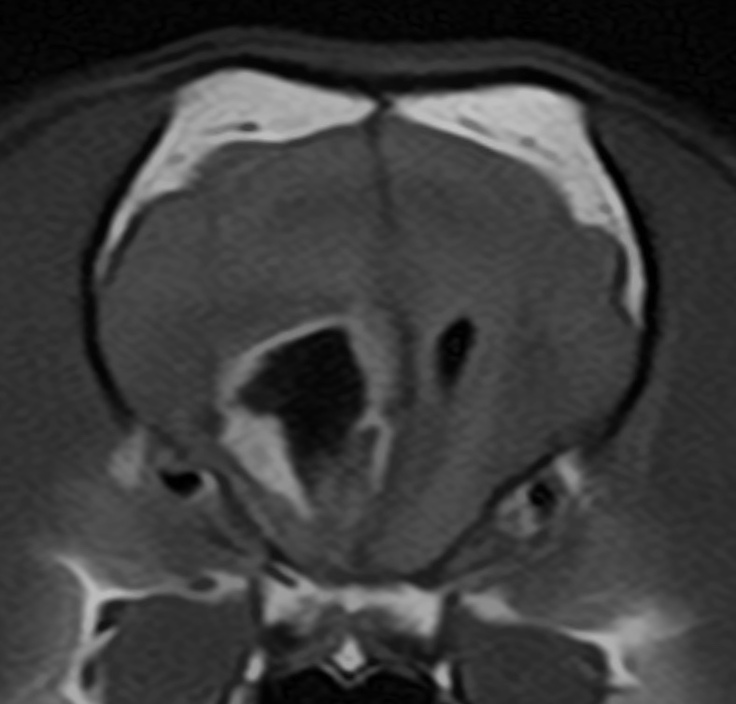

ついに昨日、京都のKyotoAR(神志那先生)にて岡山にお住まいのフレンチブルさん(7歳;手術前の画像を載せます)の前頭葉内に発生したグリオーマに対し摘出手術が行われ、皆様のご寄付により購入したカルムスチン脳内留置剤が使用されました。手術は大変うまく行われていました(手術後の画像は研究結果としての報告が控えておりますのでまだ公開はできません。すみません)。経過についてはまたいずれ。。。